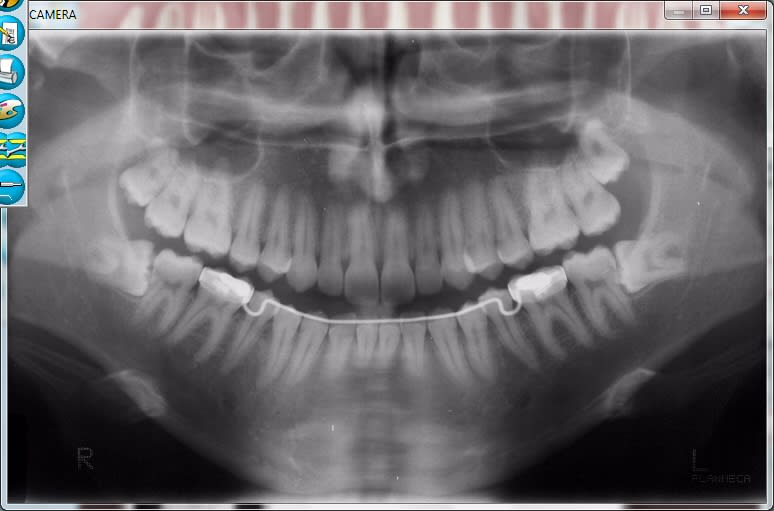

> Pour répondre à ta question : il faut poser l'indication. Quand les germes sont

> encore dans la branche à 16 ans (comme sur ta pano), il y a de forte chance

> qu'il n'y ait pas de place... Pour les autres on surveille.

perso, je ne pose pas mes diagnostics sur des pourcentages de chance , mais on peut discuter , je pense qu’un one beau montrerait une position linguale des germes et une position bien moins « postérieure » que la pano one le laisse penser. J’essaierai de suivre le cas.